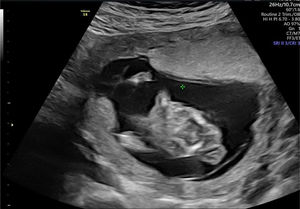

En la ecografía realizada al día siguiente en la consulta se objetivó un feto único en situación transversa izquierda con movimientos cardíacos fetales positivos. Se visualizó un encefalocele occipital de gran tamaño (fig. 1), con un defecto de la calota a nivel occipital y herniación importante de las estructuras cerebrales. En el extremo del encefalocele se objetivó una banda amniótica conectada al amnios (fig. 2). Asimismo, presentaba una ectopia cordis, con un importante defecto de la formación de la pared torácica anterior, ubicándose el corazón en el exterior de la caja torácica. En el estudio del corazón se visualizó que presentaba hipoplasia del ventrículo izquierdo. También se observó un gran defecto a nivel de la pared abdominal anterior, presentando gastrosquisis de gran cantidad de asas de intestino delgado y gran parte del hígado (fig. 3). Por último, a nivel de la columna se visualizó una cifoescoliosis severa a nivel lumbar (fig. 4). A nivel de placenta y anejos, la placenta se encontraba insertada en la cara anterior del útero con ecogenicidad acorde a la edad gestacional. En lo referente al amnios, este presentaba un fallo en la fusión con el corion (fig. 5). La cantidad de líquido amniótico era normal. No se encontraron otros hallazgos en la exploración ecográfica.